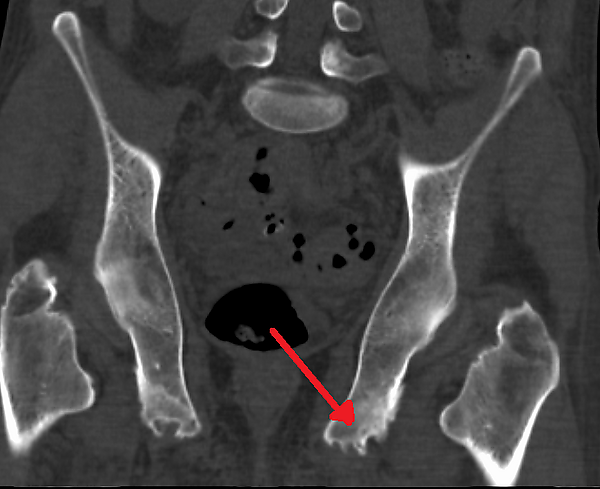

Для исследования нарушений в мягких тканях, окружающих суставы, применяется магнитно-резонансная томография. При патологических процессах легкой степени выполняют УЗИ-исследование. Рентгенография на этом этапе развития заболевания неинформативна. Однако, при наличии явных деструктивных процессов, на снимках можно увидеть очаги патологического окостенения, эрозивные повреждения, участки размягчения кости и периостит[4].